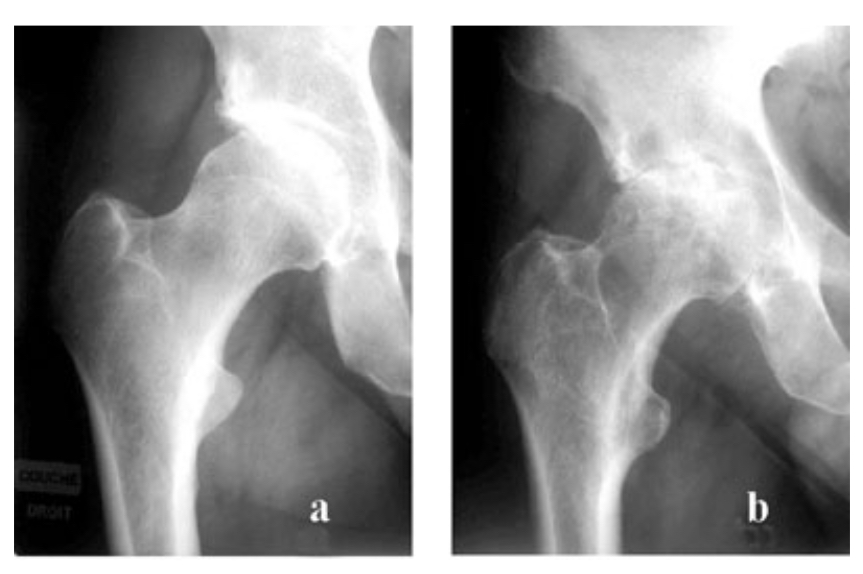

ARTHRITE SEPTIQUE

= prolifération intra-articulaire d’un micro-organisme cultivable → urgence dia +++ (dégradation cartilagineuse rapide avec séquelles + risque de septie sévère

Diag :

radio : pincement diffus de l’interligne articulaire avecérosion osseuses sous-chondrales, sans ostéophytes si abs de ttt